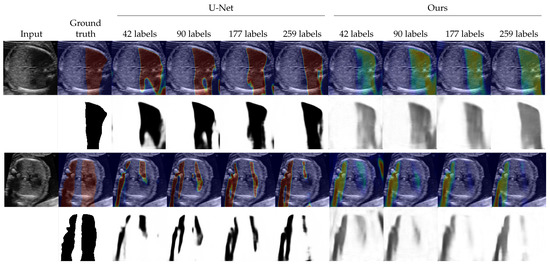

| Method | 0 | 42 (5 Videos) | 90 (10 Videos) | 177 (20 Videos) | 259 (30 Videos) |

| Geometric method [19] | 0.201 (±0.213) | - | - | - | - |

| Random walk [20] | 0.349 (±0.151) | - | - | - | - |

| U-Net [30] | - | 0.539 (±0.220) | 0.575 (±0.215) | 0.636 (±0.176) | 0.657 (±0.181) |

| Ours | 0.491 (±0.180) | 0.615 (±0.176) | 0.640 (±0.201) | 0.676 (±0.157) | 0.692 (±0.172) |